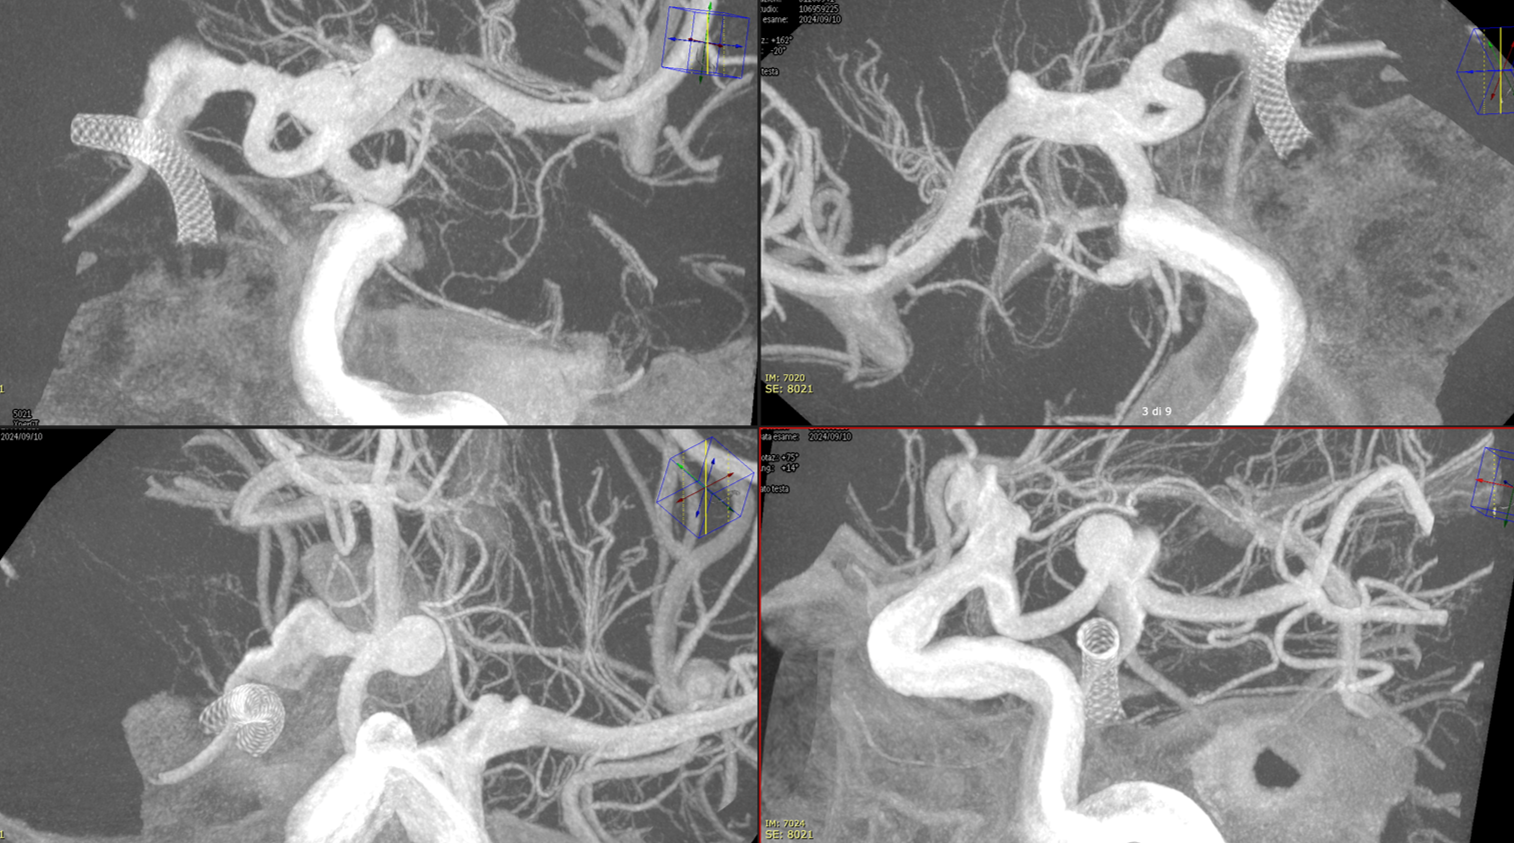

Not injected Vaso-CT, 22 cm FOV 20 seconds acquisition, followed by a secondary reconstruction with 50% FOV and 5123 resolution; Thick MIP. In this case, a Pcom aneurysm, a Derivo 2Heal was used. After the stent release, a minimum distal fish mouthing was seen, so we decided to immediately add a Pegasus stent.

We can see the struts of the Pegasus irregularly open in the carotid bifurcation. We can even recognize the typical distal end of the Derivo with the folded wires.

Noncontrast Vaso-CT, 22 cm FOV 20 seconds acquisition, followed by a secondary reconstruction with 50% FOV and 5123 resolution; Thick MIP.

Noncontrast / dry Vaso-CT, 22 cm FOV 20 seconds acquisition, followed by a secondary reconstruction with 50% FOV and 5123 resolution; Thick MIP.

We can clearly see the three stents. The Credo seems too rigid and probably is not fully open in the curve. The Bentley (arrows) is a little bit overinflated (consider that at this level the coils reduce the image quality). SV is open with some irregularity.

This is the problem with using laser-cut stents for fishmouthing. Alternative is a relatively low coverage braided stent like Evo or LVIS Jr.